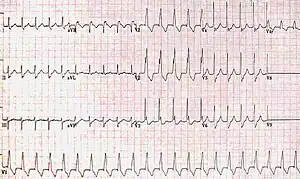

| ECG characteristics of a typical RBBB showing wide QRS complexes with a terminal R wave in lead V1 and a prolonged S wave in lead V6. | |

Diagnosis requires that the QRS complex is greater than 120 ms and an rsR' wave is present in lead V1 or V2.[2] The T waves are generally flipped in V1 and V2.[2] When the QRS duration is less than 120 ms, but the other criteria are present, it is called an incomplete RBBB.[1] Its presence does not interfere with the diagnosis of a heart attack.[1]

The criteria to diagnose a right bundle branch block on the electrocardiogram:

- The heart rhythm must originate above the ventricles (i.e., sinoatrial node, atria or atrioventricular node) to activate the conduction system at the correct point.

- The QRS duration must be more than 100 ms (incomplete block) or more than 120 ms (complete block).[4]

- There should be a terminal R wave in lead V1 (often called "R prime," and denoted by R, rR', rsR', rSR', or qR).

- There must be a prolonged S wave in leads I and V6 (sometimes referred to as a "slurred" S wave).

The T wave should be deflected opposite the terminal deflection of the QRS complex. This is known as appropriate T wave discordance with bundle branch block. A concordant T wave may suggest ischemia or myocardial infarction.